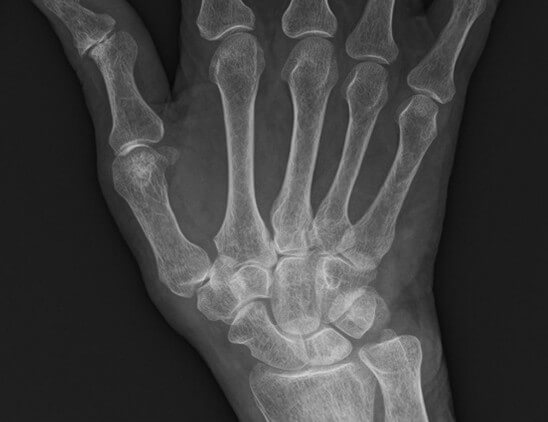

X線検査では、RAが進行すると関節周囲の骨粗鬆症に加えて、関節裂隙の狭小化、骨びらん、強直などがみられます。しかし、RA発症の初期(図1、図3)ではこうしたX線の変化はほとんどみられません。関節エコー検査(図2)やMRI検査(図4)を用いるとX線検査では認めることのできないRAの早期の変化である活動性滑膜炎や骨びらんを確認することができるので、RAの早期診断と早期治療につながります。